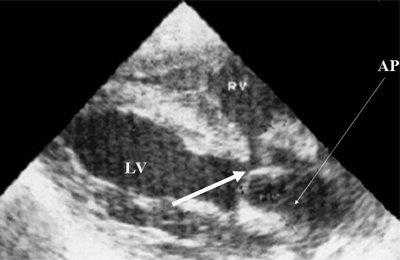

Характерными особенностями выраженной объемной перегрузки правого желудочка являются дилатация желудочка, при которой толщина миокарда не превышает верхней границы нормы, увеличение правого предсердия, парадоксальный характер движения межжелудочковой перегородки и увеличение амплитуды движения трикуспидального клапана (рис. 2, 3).

Рис. 2. Длинная ось сердца. Объемная перегрузка правого желудочка при дефекте межпредсердной перегородки. Объем сброса крови превышает 200% МОС. Отмечается выраженная дилатация правого желудочка.

Рис. 3. Объемная перегрузка правого желудочка при дефекте межпредсердной перегородки. В- и М-сканирование. Стрелкой показан парадоксальный характер движения межжелудочковой перегородки.